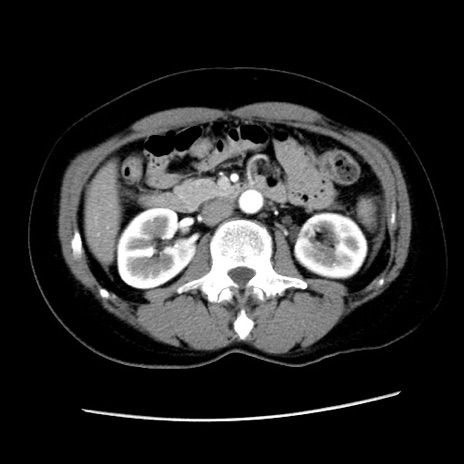

冠状断像

【症例】 50歳代女性

【主訴】 腹痛

【現病歴】前日生レバーを食べた。今朝に排便あり。 昼前に突然発症の腹痛を生じ、当院救急外来を受診した。

【身体所見】 意識清明、腹部:平坦、軟、下腹部やや左を中心に圧痛・反跳痛あり、筋性防御あり

【データ】WBC 7800、CRP 0.07